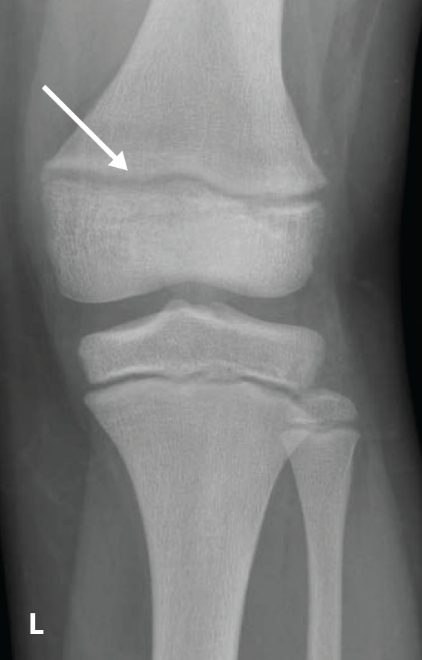

The RSS is a quantitative method that uses radiographs to assess the severity of rickets at the wrists and knees. Originally validated in nutritional rickets, the score is based on the degree of metaphyseal fraying, metaphyseal cupping, and the proportion of the growth plate that is affected. It is a 10-point scale, for which 10 represents the most severe radiographic changes due to rickets and 0 represents the absence of these changes.1

Although the severity and duration of rickets vary considerably between XLH and nutritional rickets, the radiographic features of rickets at the growth plate are similar in the two disorders, which allowed validation of the RSS in XLH. The RSS correlates with serum alkaline phosphatase (ALP) levels, a biochemical marker of rachitic activity, and this scoring system can be used to assess the radiographic response following treatment of nutritional or XLH rickets.

The RSS in XLH has been reported to range from 0 to 4.5; however, despite the smaller RSS range observed in XLH patients, inter- and intra-rater reliability are similar to those reported for nutritional rickets. Patients with XLH who had a baseline RSS ≥1.5 were shown to have more severe hypophosphatemic bone disease, including higher levels of alkaline phosphatase, and greater impairments in clinical outcomes compared with patients who had a baseline RSS <1.5.